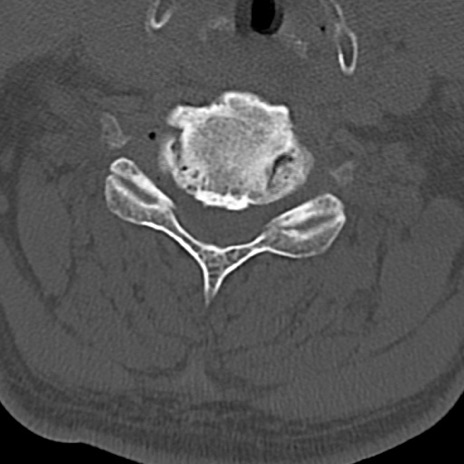

頚椎CT

横断像